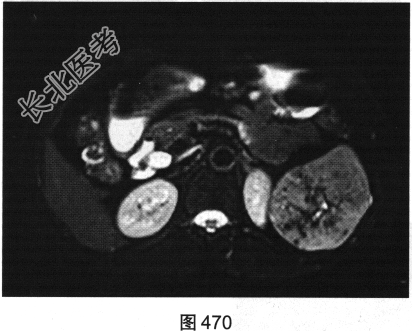

- 多项选择题4.[提示]为进一步明确诊断,患者行MRI检查, 如图470~图473所示。对MRI图像描述正确的是( )

A、T1WI呈不均匀稍低信号

B、左肾被病灶侵犯

C、病灶内见树枝状T1WI低信号、T2WI低信号影

D、门脉期可见造影剂进一步持续充填

E、动脉期轻度强化

F、抑脂T2WI呈不均匀稍高信号